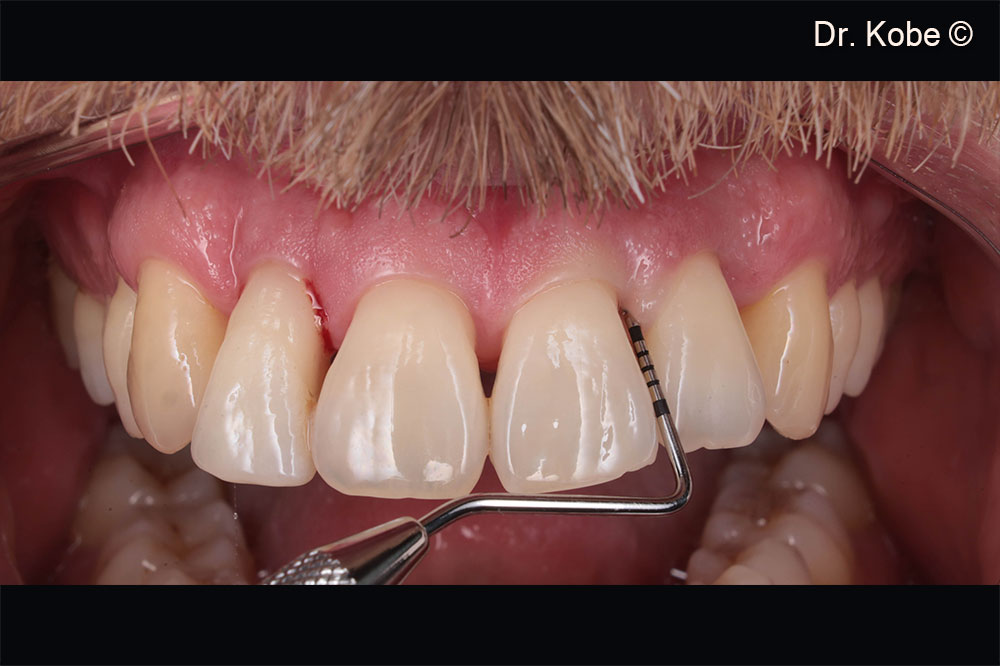

Vết thương lành hoàn toàn

Theo dõi một năm ở góc phần tư thứ nhất

Theo dõi một năm ở góc phần tư thứ hai